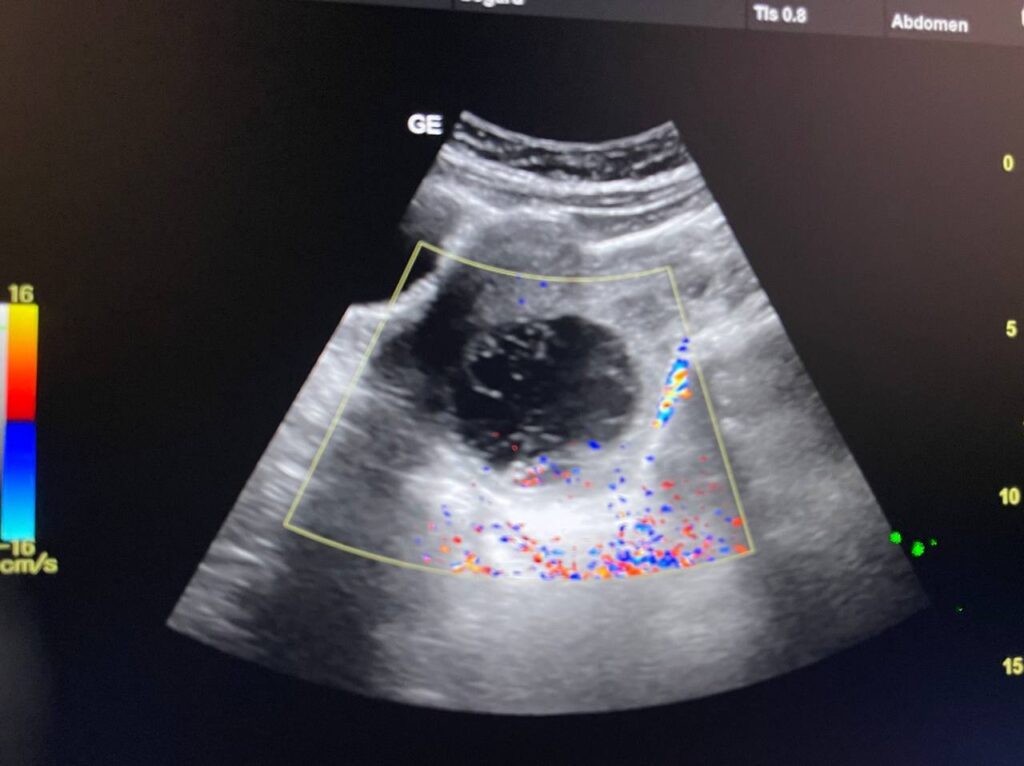

Right ovarian heterogeneous circumscribed avascular cystic mass its size 55x55mm, mostly hemorrhagic , with whirlpool sign , picture mostly of Twisted right hemorrhagic ovarian cystic , Cystic TORSION , please for further study ??

· No free pelvic fluid seen